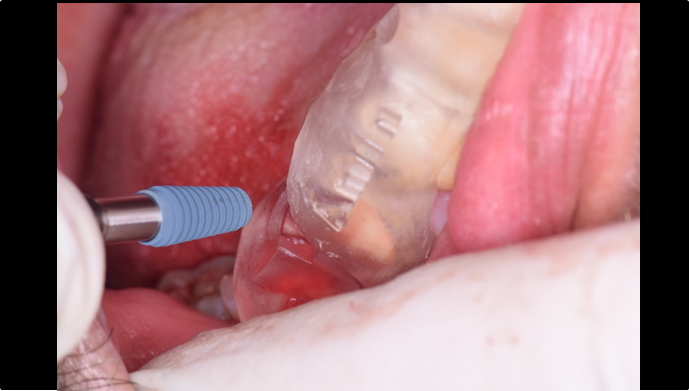

Clinical case: : Immediate loading of lower molars using R2Gate prefabricated 3D-printed provisional restoration

- Courtesy of Dr. Sam Omar, Egypt -